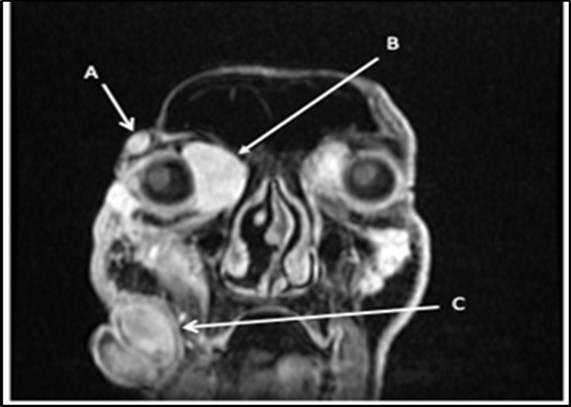

With the previous biopsy done 5 months ago, the primary working impression is neurofibromatosis. These types of lesions tend to be painless, slowly growing, solitary, skin-colored, soft, flaccid, rubbery to firm papules or nodules with a smooth surface measuring up to 2 cm. Classic characteristics include a “bag-of-worms” consistency and eyelid involvement producing an S-shaped deformity in cases of the plexiform variants1. The lesion also invaginates with pressure. The prevailing diagnostic criteria of Figure 2. Multiple facial lesions are radiologically consistent with neurofibromas. (A) 1.8x0.9x1.7cm right lateral temporal mass (B) 3.2x3.3x4.5cm right medial intraorbital mass (C) 8.6x7.3x6.0cm right nasal mass neurofibromatosis type 1 are met if 2 or more of the following are present: (1) ≥ 6 café au lait patches (2) ≥ 2 neurofibromas of any type, or 1 plexiform neurofibroma (3) axillary or inguinal freckling (4) ≥ 2 lisch nodules, (5) optic glioma, (6) sphenoid dysplasia or thinning of long bone cortex with or without pseudoarthrosis (7) first-degree relative diagnosed with neurofibromatosis type12. In contrast to this, our patient did not satisfy any clinical manifestations of Neurofibromatosis type 1. The closest differential of neurofibroma would be a schwannoma. If present on the orbit, they are insidious and proptose gradually without pulsations. Most tumors infiltrate the superior quadrant, causing inferiorly displaced proptosis or frank hypoglobus3. Patients may experience diplopia, eye movement limitation, diminished visual acuity, and optic nerve compression symptoms, including scotomas dyschromatopsia, and impaired contrast sensitivity. They may also experience pain or paresthesia in the distribution of the nerve. In severe cases, there may be a palpable orbital mass4. Only one case has been reported of a bilateral orbit involvement5. Another differential would be the malignant transformation of neurofibroma. Malignant peripheral nerve sheath tumor may arise from a preexisting nerve sheath tumor in neurofibromatosis type 1 and can arise in virtually any anatomic location. The most common sites are the trunk and extremities, followed by the head and neck. There is no gender preference, and it tends to occur in younger individuals with Neurofibromatosis1. Histologic evaluation is necessary but not always specific and requires correlation with clinical and radiologic findings6. At this point, the clinical presentation is consistent with the previous histopathologic diagnoses, that of a neurofibroma. Although a neurofibrosarcoma would also have a similar presentation at its early stages, its predilection for arising from NF type 1 lesions is not seen in our patient.

Figure 2.Multiple facial lesions radiologically consistent with neurofibromas. (A) 1.8X0.9X1.7cm right lateral temporal mass (B) 3.2X3X4.5 cmright medial intraorbital mass (B) (C) 8.6X7.3X6.0 cmr right nasal mass